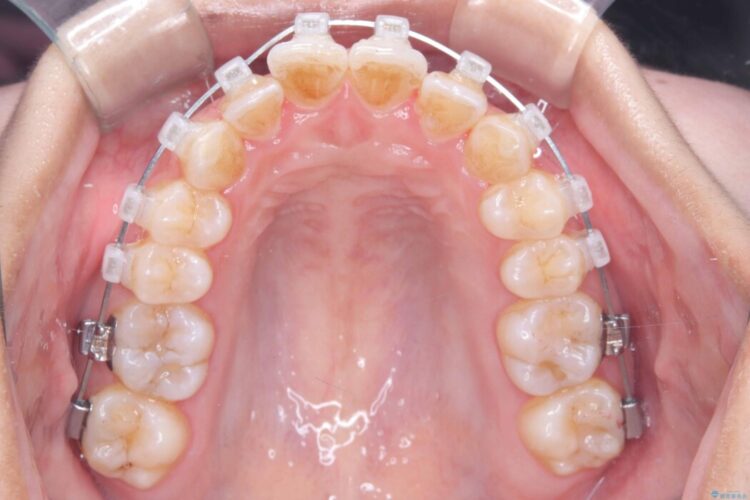

- 矯正装置:クリア装置 ワイヤー

歯の移動量や力のコントロールを最適化することで、短期間で治療完了しました。

「矯正は時間がかかる」というイメージをお持ちの方も多いですが、症例によっては、非抜歯でも短期間で改善が可能な場合があります。

治療後は歯並び・かみ合わせともに大きく改善し、患者様にも大変ご満足いただけました。